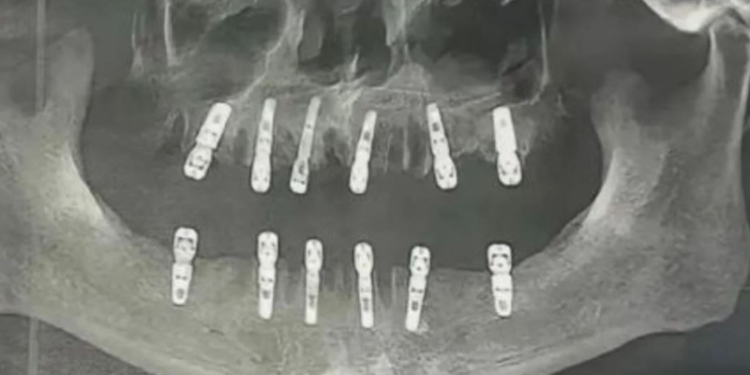

Um homem morreu 13 dias depois de extrair 23 dentes e implantar 12, na mesma cirurgia. O caso foi registrado na Yongkang Jinhua, na China, no dia 27 de agosto.

De acordo com a mídia local, o homem foi vítima de uma parada cardíaca. A causa da morte está sendo investigada pelo Departamento Municipal de Saúde de Yongkang. Conforme os relatos, o paciente assinou o termo de consentimento para a cirurgia. Após o procedimento, o homem continuou sentindo dores e morreu dias depois. O procedimento dentário teria custado 1.500 yuans (cerca de R$ 1.185) por dente, o que equivale a aproximadamente R$ 27 mil. Conforme o hospital onde ocorreu o procedimento, o médico responsável tem cinco anos de experiência.

De acordo com especialistas, o número máximo de dentes que podem ser extraídos de uma vez é de 10. A filha do da vítima planeja entrar com uma ação judicial contra o hospital.